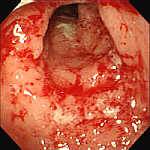

Leziunile precoce sunt granularitatea mucoasei, cu stergerea luciului si hiperemie. Apar ulterior ulceratii mici, superficiale, care cresc progresiv in dimensiuni. In fazele active pot fi acoperite de exudat muco-purulent sau hemoragic. In zonele de confluenta a ulceratiilor apar si denivelari - pseudopolipi inflamatori -zone de regenerare a mucoasei,cu tesut de granulatie, ce nu se malignizeaza.

RCUH - stadializare endoscopica

STADIUL 3 (activitate severa ) |

Mucoasa hiperemica, edematiata, cu ulceratii multiple de dimensiuni variabile (2-4 mm), superficiale, neregulate, care sangereaza difuz la atingerea cu endoscopul, acoperite pe alocuri de exudate mucopurulente si hemoragice |

Stadiul 1 Stadiul 2 Stadiul 3